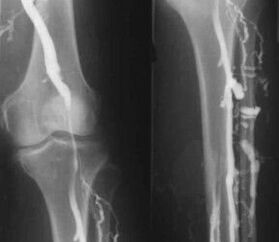

A leggyakoribb műszeres diagnosztikai módszer a lábak vénás ereinek ultrahangvizsgálatának alkalmazása. Ez a technika lehetővé teszi az érrendszer megjelenítését és a kóros folyamat előrehaladásának mértékének azonosítását.

- Flebográfia.

A vénás elzáródásos pletizmográfia alkalmazása lehetővé teszi az alsó végtagok vénáiban lévő vér mennyiségének meghatározását.